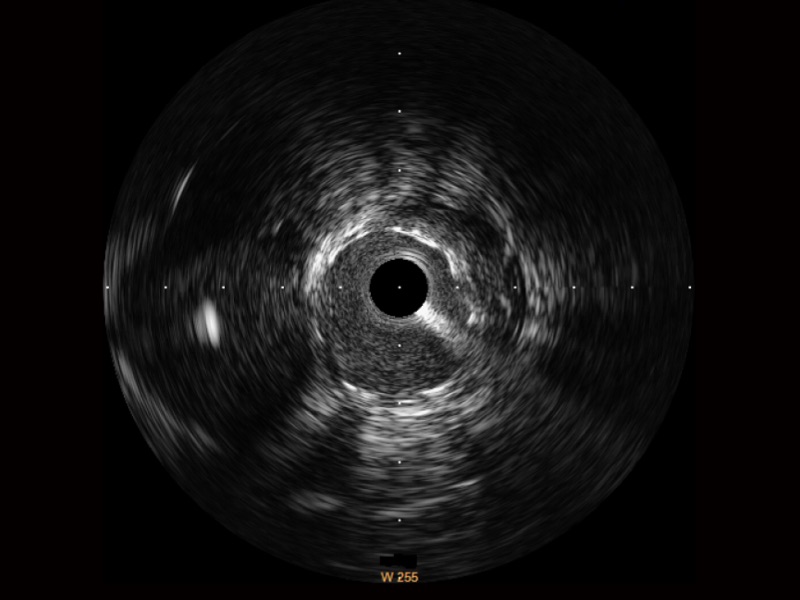

• 新葡的京集团8814检测站宽频IVUS图像

• 传统IVUS图像

对比传统IVUS导管成像,新葡的京集团8814检测站宽频IVUS图像的近场支架梁显影更细腻,远场中膜外血管仍清晰可辨,兼顾远中近,兼顾分辨力与穿透深度